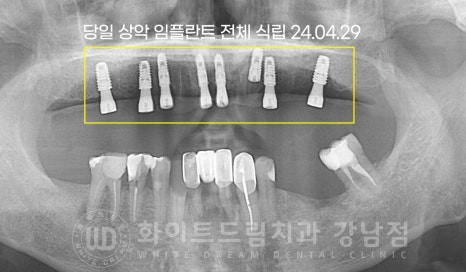

환자분은 수술 3개월 뒤 정기검진 시 임플란트의 고정력이 안정적이게 확인되어

당일 23번 임플란트 2차 수술을 진행하였고

임플란트 보철 제작을 위한 인상채득과정을 진행하게 되었습니다.

전악 보철 제작 기간은 약 10일 정도 소요되며

제작된 전악 보철을 당일 모두 체결하게 됩니다.

체결된 보철을 짧으면 2주 길게는 2-3달 정도 사용하시면서

불편하신 점이 없는지 확인하는 과정을 거치게 됩니다.

이 기간 동안 별다른 불편함이 없으시다면 임플란트 보철을 영구 접착하며

치료는 종료되게 됩니다.

기간 : 24.04.29 - 24.10.10

이렇게 잃어버린 전체 치아를 다시 완성하는데

수술 후 총 5회의 내원만 해주셨고

전체 임플란트 치료 기간도 6개월이 채 되지 않게 완료가 되었습니다.